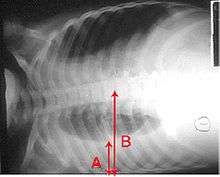

A pleural effusion appears as an area of whiteness on a standard posteroanterior chest X-ray.[5] Normally, the space between the visceral pleura and the parietal pleura cannot be seen. A pleural effusion infiltrates the space between these layers. Because the pleural effusion has a density similar to water, it can be seen on radiographs. Since the effusion has greater density than the rest of the lung, it gravitates towards the lower portions of the pleural cavity. The pleural effusion behaves according to basic fluid dynamics, conforming to the shape of pleural space, which is determined by the lung and chest wall. If the pleural space contains both air and fluid, then an air-fluid level that is horizontal will be present, instead of conforming to the lung space.[6] Chest radiographs in the lateral decubitus position (with the patient lying on the side of the pleural effusion) are more sensitive and can detect as little as 50 mL of fluid. At least 300 mL of fluid must be present before upright chest X-rays can detect a pleural effusion (e.g., blunted costophrenic angles).